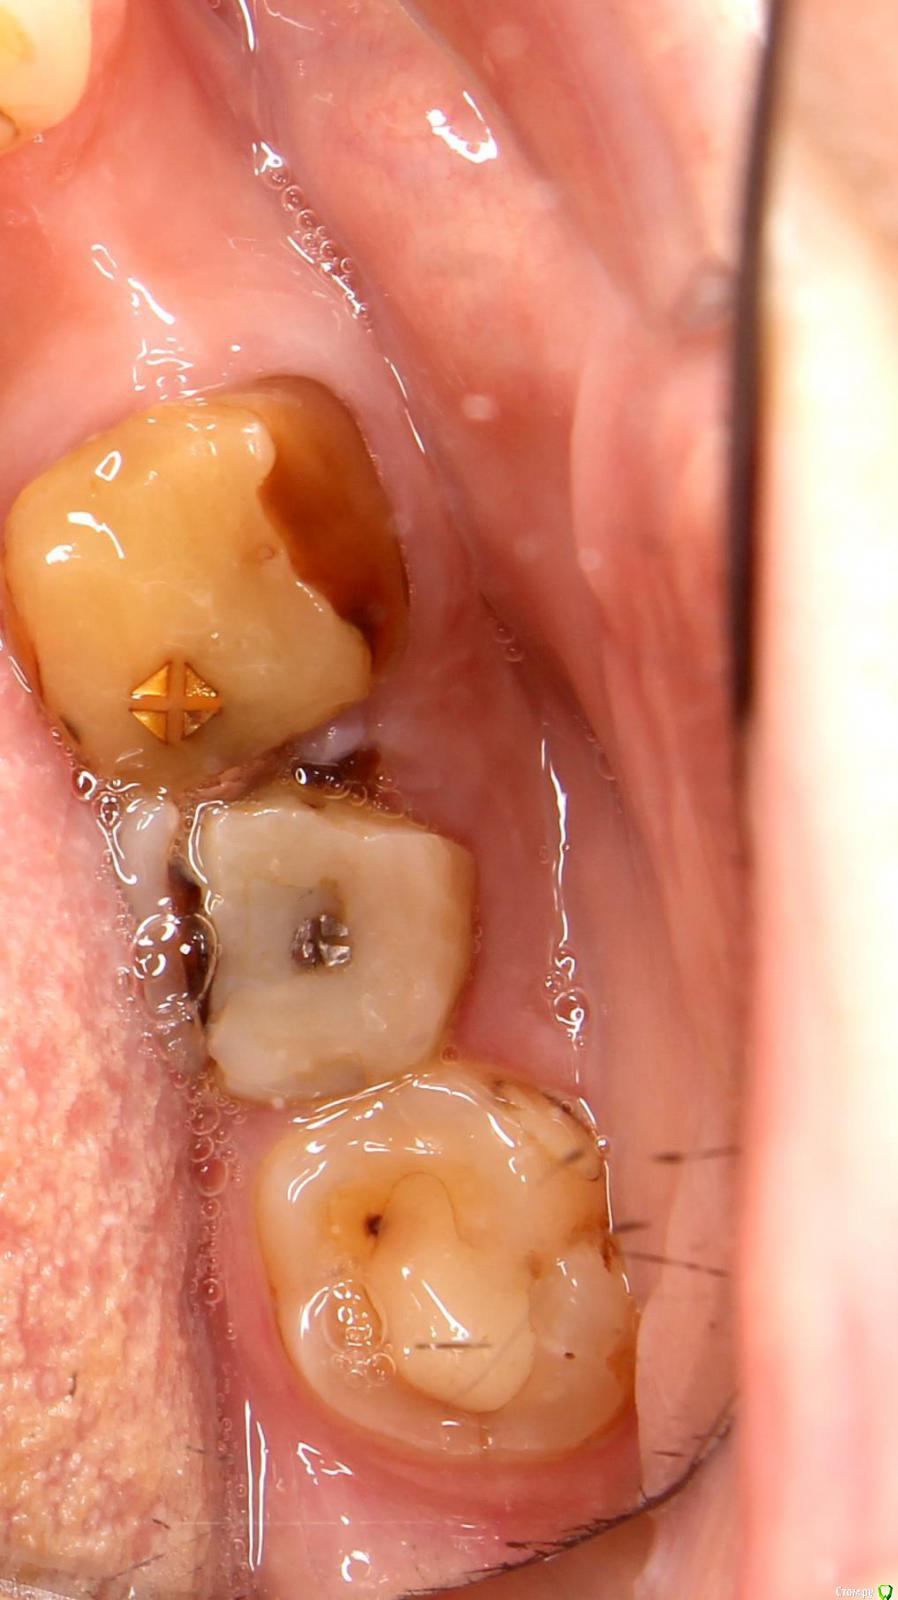

37-й зуб. Депульпирован, стояла большая пломба. В 2013 году  откололась наружная стенка зуба, скол близко к корню. Стоматологом № 1 был поставлен штифт, коронка восстановлена пломбой (фото с торчащим штифтом от 2013 года). Через год наружная часть пломбы откололась прямо по штифту, так ходила три года, ничего не царапало, не мешало. В 2016 году стоматолог № 2 в поликлинике уговорила запломбировать, в результате сделала скошенную наружную часть пломбы. Фото ротовой полости справа от 07.2019 г. прилагаю.

Вопрос: что делать с 37-й зубом? Хирург не хочет удалять, говорит, что можно восстановить пломбой, и боится повредить 36-й. Не знаю, видно ли на снимках, в каком канале стоит штифт и можно ли поставить еще один штифт (второй штифт врач не поставила, насколько я помню, из-за того, что будет дороже и еще что-то там может не выдержать). Без второго штифта пломба, повторяющая анатомическую форму зуба, я считаю, простоит максимум год. С 36-м зубом тоже непонятно что делать, не идет ли там процесс кариеса на корне…